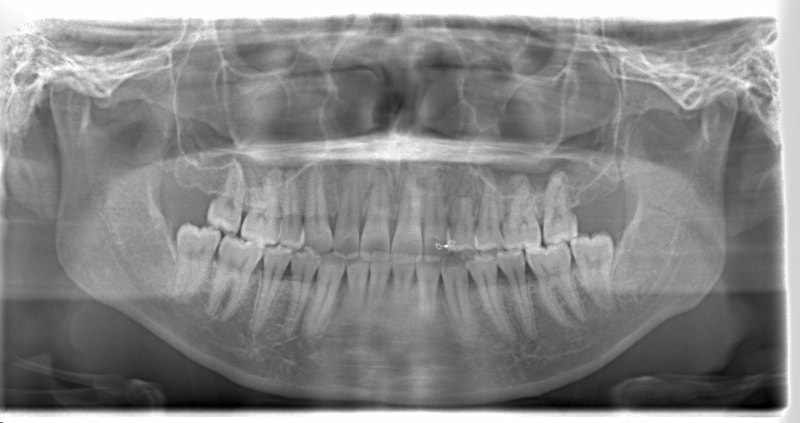

治療後(2年後)

治療開始から24ヶ月後